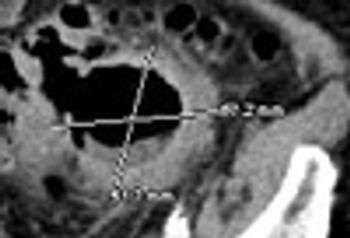

A 76-year-old man presented with left-sided chest pain, after a fall. He had tenderness along the left 8th rib and left basal rales. CXR showed non-displaced fractures of the 7th and 8th ribs with a small effusion and a right postero-basal rounded opacity.